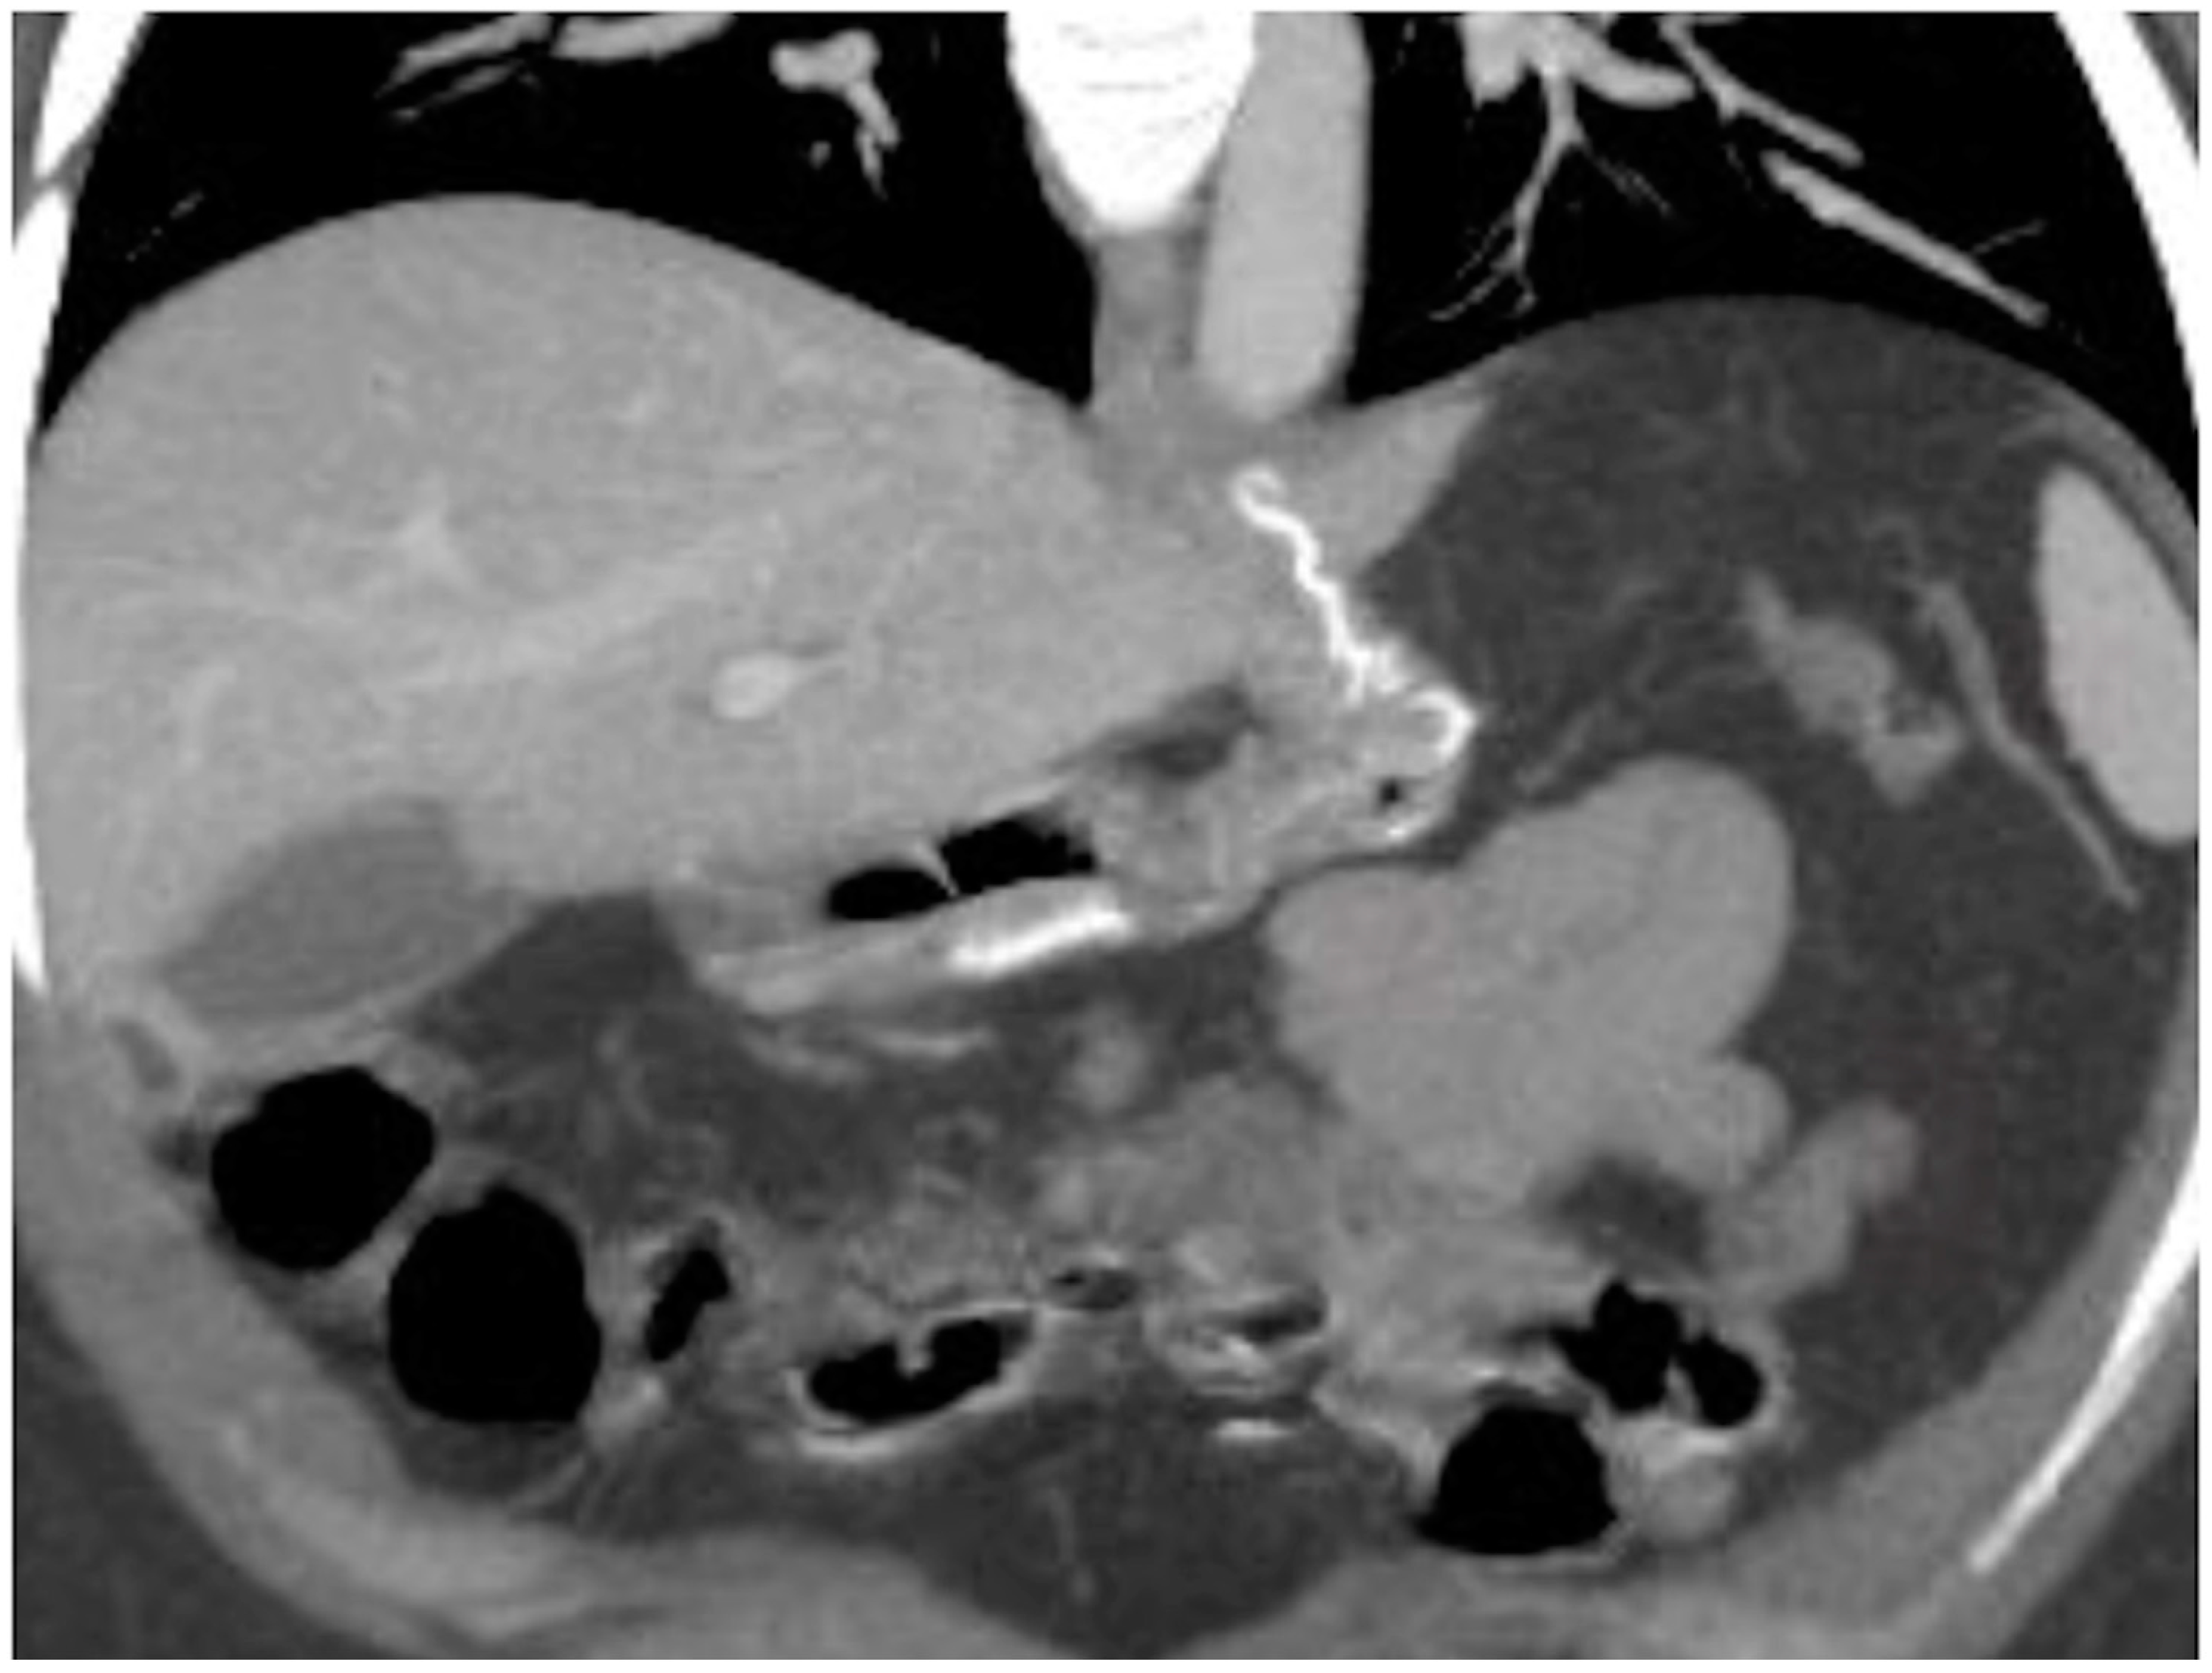

Figure 15. Spleno-portal thrombosis and liver abscesses after sleeve gastrectomy with suture leak. A 46-year-old female with a type I leak after sleeve gastrectomy complained of abdominal pain, fever and kidney failure. Note the gastric surgical suture (a, coronal oblique view), the presence of a type I leak (b, axial view, straight arrow), and of multiple liver abscesses (bd, axial view, curved arrows) related to extensive spleno-portal thrombosis (df, straight arrows). The leak is responsible for spread of gastric content and bacteria, causing septic spleno-portal thrombosis and, consequently, liver abscesses. The leak was conservatively treated and the thrombosis was successfully treated with multiple sessions of transhepatic catheter-directed thrombolysis.

• Spleno-porto-mesenteric vein thrombosis (PVT)

The described incidence is around 0.3%. PVT is difficult to recognize, and symptoms are vague and not specific, but consequences are significant. This complication can occur in any of the other mentioned obesity laparoscopic treatments, but the incidence after SG is higher, probably due to the ligation of gastroepiploic vessels or short gastric vessels. During this procedure, performed in close proximity to the splenic vein, it may occur as a mechanical injury to the vein as a possible cause of thrombosis; another possible cause of thrombosis may be the alteration of venous return from the stomach. It may also occur as a consequence of post-discharge dehydration and hypovolemia [7].

Imaging findings:

Color Doppler Ultrasound may detect flow defects in explorable vessels; however, CT has major panoramicity and is suggested as the first imaging examination in these patients (Figure 15) as it can depict in detail the extension and severity of the thrombotic defects [7].